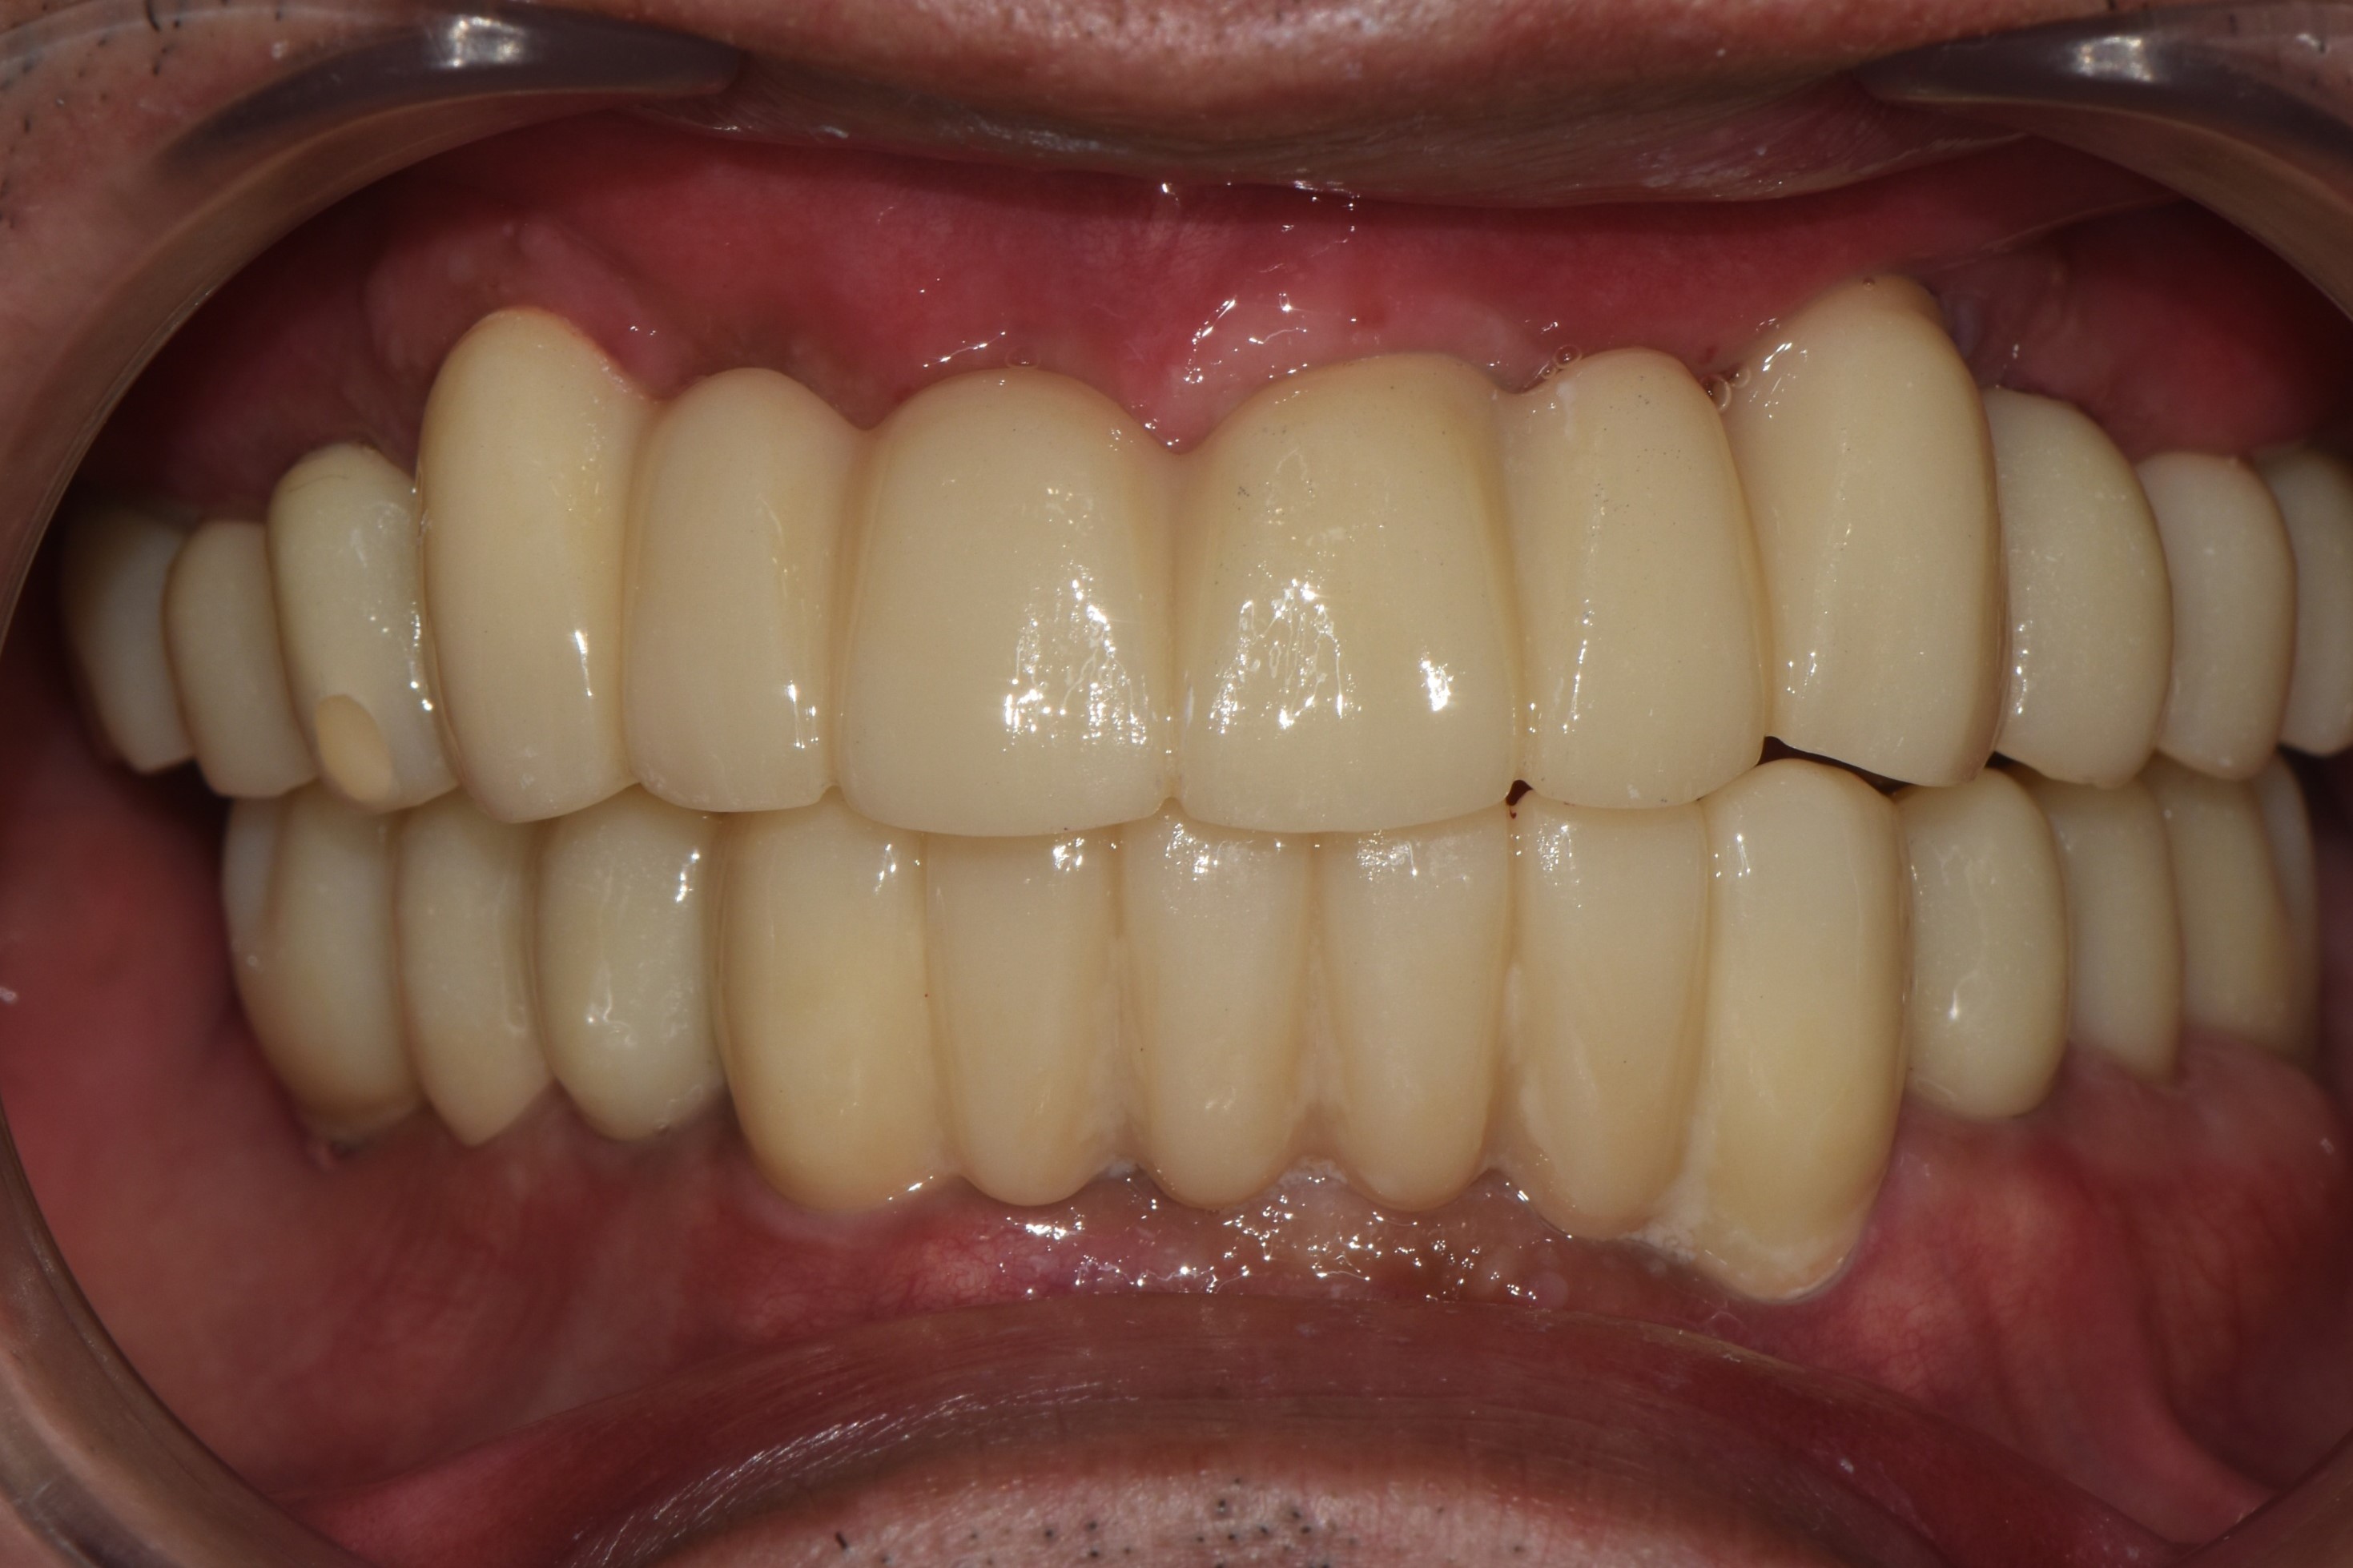

촬영일시: 2025.10.01 [ 치료기간: 2025년 05월 27일 ~2025년 10월 01일 ] ※ 365서울앞선치과의원의 모든 컬럼은 각 진료과 의료진이 직접 작성합니다. 365서울앞선치과의원 임상 케이스 게시물은 환자분께 의학적으로 정확하고 상세한 정보를 드리기 위해 각 진료과 의료진이 직접 작성하며, 모든 증례 사진은 본원 의료진이 직접 시술한 증례를 촬영한 것으로, 의료법 제23조, 제56조에 의거하며 환자분의 동의를 얻어 포스팅에 사용하였습니다. 또한 해당 케이스는 본 환자분의 치료 결과이며, 환자 상태에 따라 치료의 결과는 달라질 수 있습니다. |